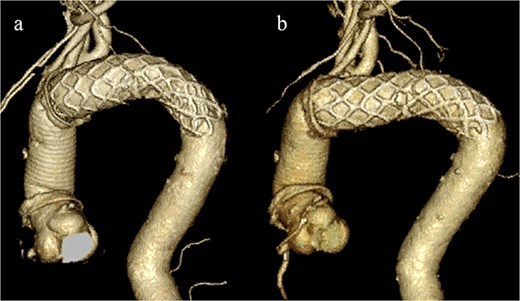

Given the ongoing hemoptysis, presumed aneurysmal expansion due to an occult endoleak, and the absence of any other obvious causes of hemoptysis, we determined that intervention for the aneurysm was necessary. TEVAR was performed using a right femoral artery approach. Initial angiography did not reveal contrast leakage into the sac (Fig. 3a). A 34 × 34 × 200 mm Gore Conformable TAG stent graft (W.L. Gore & Associates, Flagstaff, AZ, USA) was deployed to cover the distal edge of the FET. The second stent graft, a 34 × 34 × 150 mm Gore Conformable TAG stent graft, was deployed overlapping the first graft immediately after the left subclavian artery branch to cover the entire length of the FET (Fig. 3b). Considering the proximal migration, a type Ib endoleak was deemed the most likely cause. However, the possibility of a type III endoleak from the graft was also considered, so the stent graft was deployed to cover the entire area. The patient’s hemoptysis resolved completely postoperatively. A follow-up CT 2 years later showed a reduction in the aneurysm size from 56 to 44 mm (Fig. 4).

(a) Contrast-enhanced CT performed soon after TEVAR showing an aneurysm diameter of 56 mm. (b) Two years later, contrast-enhanced CT showing a reduction in the aneurysm diameter to 44 mm.